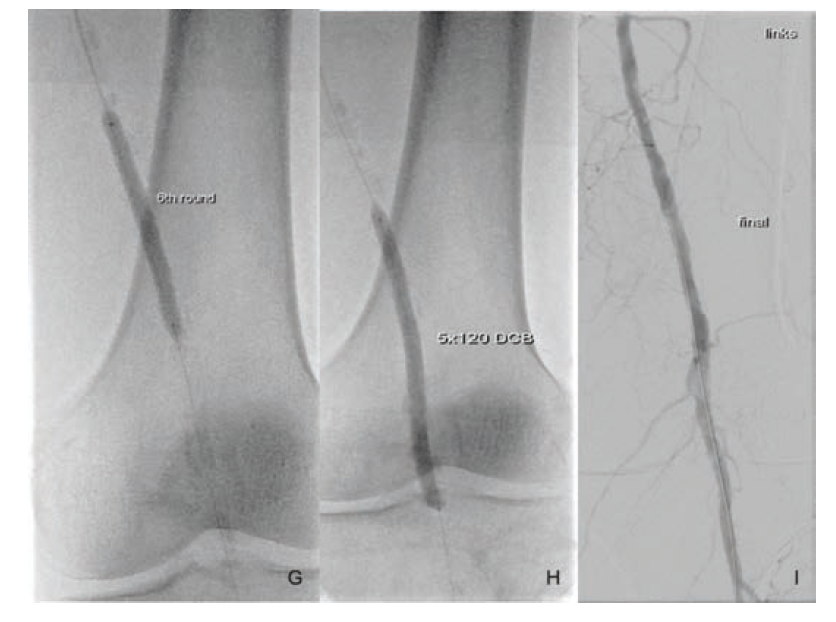

Under local anesthesia, left antegrade femoral arterial access was obtained using ultrasound guidance. After the insertion of a short 6 Fr arterial sheath (Terumo), a diagnostic angiogram was performed using the Angiodroid carbon dioxide (CO2) injector (San Lazzaro di Savena, Italy). This confirmed the preprocedural duplex ultrasound findings (Figure 1). A Choice PT 0.014 floppy wire (Boston Scientific) and a Quick-Cross support catheter (Phillips) were used to cross the lesion. After crossing the lesion, a vessel preparation with endovascular lithoplasty (Shockwave Medical, Fremont, US) was performed using a 5 × 60 mm catheter inflated to 4 atm and activated. After delivering 30 pulses, the balloon was inflated to the reference vessel diameter for an additional 120 seconds. The lithoplasty was activated an additional 6 times after repositioning of the catheter in order to treat the entire lesion from “healthy to healthy,” delivering a total of 180 pulses. An antirestenotic therapy with a drug coated balloon (DCB) (5 ×120 mm, In.Pact Admiral, Medtronic) was applied following the plaque modification. The final angiography did not show any residual stenosis, local dissection, or distal embolization. The procedure was completed with the use of 10 mL contrast medium, and the patient was discharged the following day.